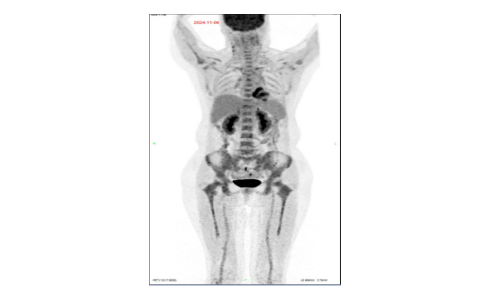

PET-CT(2024-11-07)示:全身多发淋巴结显示,部分增大伴代谢稍高,较前部分体积缩小、代谢减低,考虑肿瘤活性部分受抑,部分残留。脾略大,代谢不高,倾向反应性改变;余全身所示骨骼及髓腔代谢弥漫增高,待除外淋巴瘤浸润,建议结合骨穿。

图1. 2024-11-07 PET-CT表现